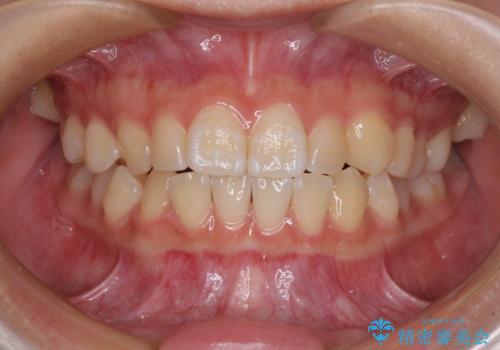

30代女性 前歯のがたつき